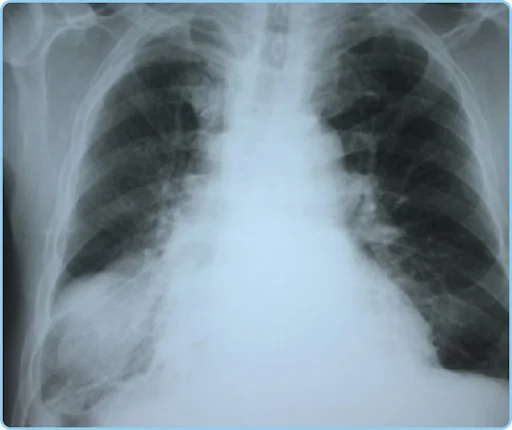

Q11. A 30-year-old male presents with fever, cough, night sweats, and unintentional weight loss over the past month. X-ray chest is taken and is shown below. What is the most probable diagnosis?

- Miliary Tuberculosis

- Pulmonary Sarcoidosis

- Mycoplasma Pneumonia

- Metastatic Lung Disease

Ans. 1) Miliary Tuberculosis